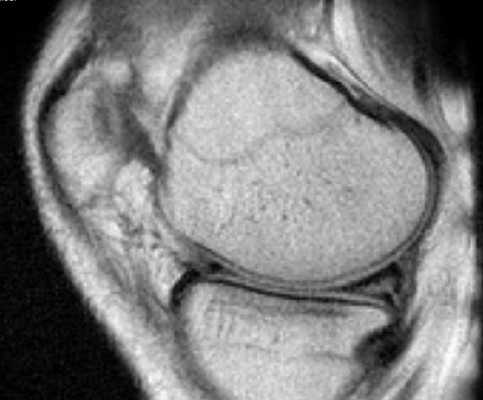

Признаком повреждения мениска служит наличие линейного гиперинтенсивного очага на Т2-взвешенных изображениях. Участок сообщается с суставной поверхностью хряща, линию разрыва прослеживают на двух и более сканируемых срезах. При этом наблюдают деформацию и фрагментацию пластины.

Томограмма коленного сустава при радиальном разрыве мениска (указан стрелкой)

В зависимости от степени повреждения на снимках МРТ в режиме Т2 видны:

- очаг повышения интенсивности сигнала шаровидной формы, не связанный с поверхностью мениска (I стадия);

- светлый участок линейной формы, не затрагивающий хрящевой край (II стадия);

- повышение интенсивности сигнала распространяется на одну (III a) или обе (III b стадия) суставные поверхности пластины.